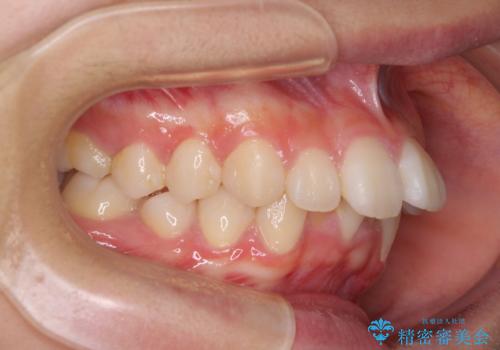

上下前歯の前後差が大きく、下顎前歯が隠れるほど深い咬合で、咬合力が強い状態でした。

深い咬み合わせの改善に時間がかかりましたが、下顎前歯がしっかりと見えるまでに整えることができ、口元の突出感も大幅に改善することができました。